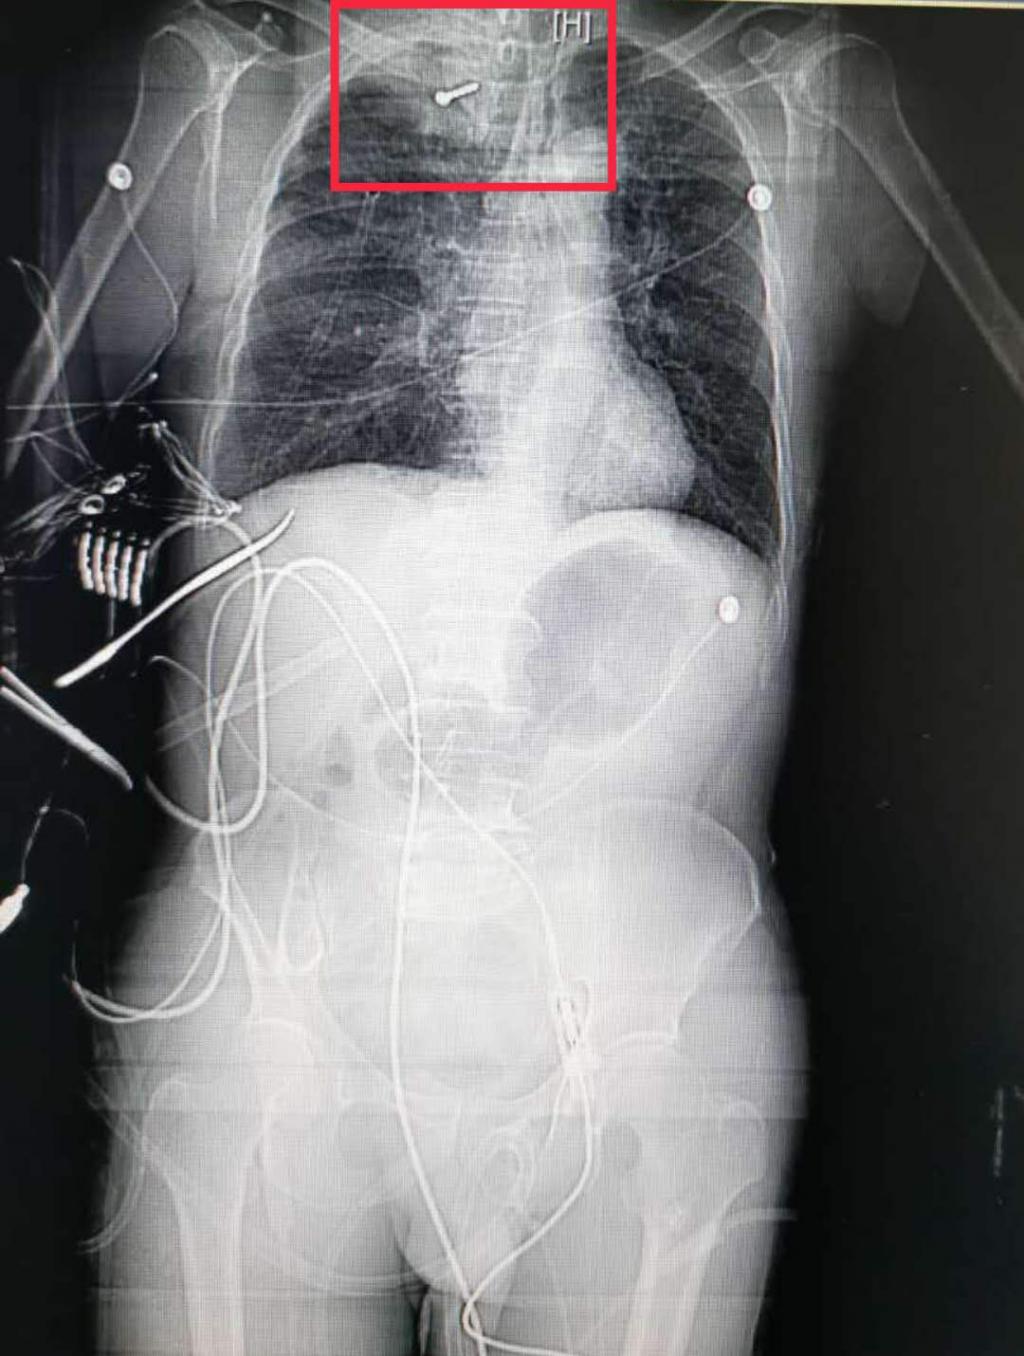

气钉枪" 走火" , 一根3CM长、直径2mm的钢钉不偏不倚地射进王师傅颈部 , 直抵肺脏 , 性命垂危 。 南华大学附属长沙市中心医院及时开辟绿色通道全力救治 , 手术成功取出钢钉 , 患者转危为安 。

入院时 , 王师傅已经出现嗜睡症状 , 右侧颈部有约4CM伤口 , 出血不止 , 患者呼吸极度困难 , 急诊CT 提示 , 金属异物存留、右上肺挫伤、肺出血 , 右颈部及右前上胸壁软组织伤、广泛气肿 。 " 钉子穿过患者颈部 , 一部分直接插入胸腔射入肺脏 , 幸运的是避开了大血管 , 但当时情况也很危急 。 " 急诊科予以紧急加压包扎胸部 , 并请胸心外科进行胸腔闭式引流术等紧急抢救 , 主任医师杨继承会诊后 , 邀请耳鼻咽喉头颈外科专家同台进行右侧开胸止血、肺内异物取出、肺修补术及颈部血管吻合术 。 手术进行了2个多小时 , 患者体内钢钉被顺利取出 , 后被转入重症监护室继续治疗 , 目前恢复情况良好 。